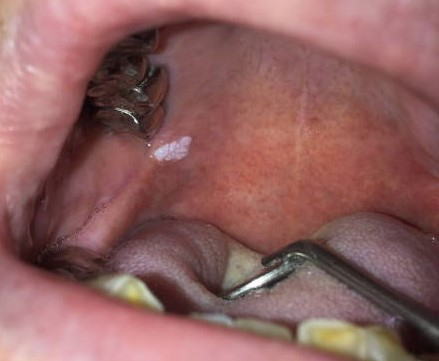

症例

症例1:一見カンジダ症にも見えますが、拭いても剥離できない白板症。